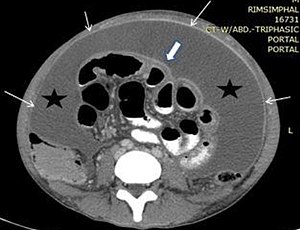

Peritoneal carcinomatosis is a stage IV cancer that affects the lining of the abdominal cavity. Peritoneal cancers are often caused by the following conditions: